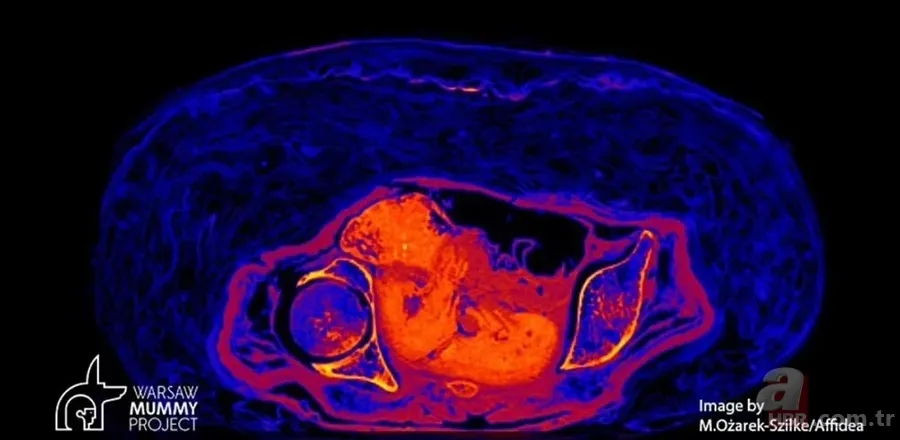

Yeni teknolojiler kullanan bilim insanları, "Gizemli Kadın" olarak adlandırılan bir Mısır mumyasının karnındaki fetüsü ortaya çıkardı. Bebeğin 2 bin yıl boyunca bozulmadan kaldığını açıklayan uzmanlar, mumyanın ölüm nedeni hala beliryemediklerini, ancak gerçek bir insanlık trajedisine ışık tuttuklarını söyledi. Peki bebek yıllarca bozulmadan nasıl günümüze kadar geldi? İşte haberin detayları...

Mısırlı bir mumyanın karnında bulunan bir fetüsün, kadının vücudunun çürürken asitlenmesi nedeniyle 2 bin yıldan uzun bir süre boyunca korunduğu belirtildi.

Polonya'daki Varşova Üniversitesi'nden araştırmacılar, geçen yılın Nisan ayında CT ve X-ray taramaları kullanarak doğmamış çocuğun kalıntılarının varlığını ortaya çıkardı.